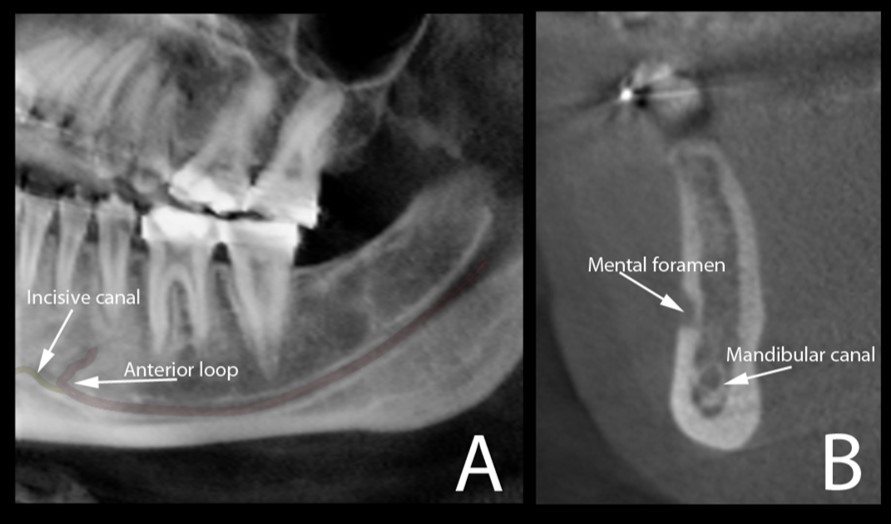

The typical images from modern human and great apes with different anatomical features were shown in Figure 1 and Figure 2. A group of variables were categorized as: the presence of the incisive canal, the number of mandibular canal bifurcations, the potential occurrence of an anterior loop, the presence of the incisive canals, its end-point and connection of the incisive to the lingual canals (Figure 3). Interspecific variability was determined by comparing contemporary human and great ape mandibles. In this analysis, mandibles from the different geographical locations were grouped in the human group, and then compared to mandibles of chimpanzees and gorillas.

Figure 3.Cone beam CT image (A) shows the oblique reconstruction of the volume of interest at the region of premolars. In this reconstruction, the anterior loop of the mandibular canal can be clearly observed before the start of the incisive canal. The appearance of this anterior loop in a cross-sectional view is shown in image (B).